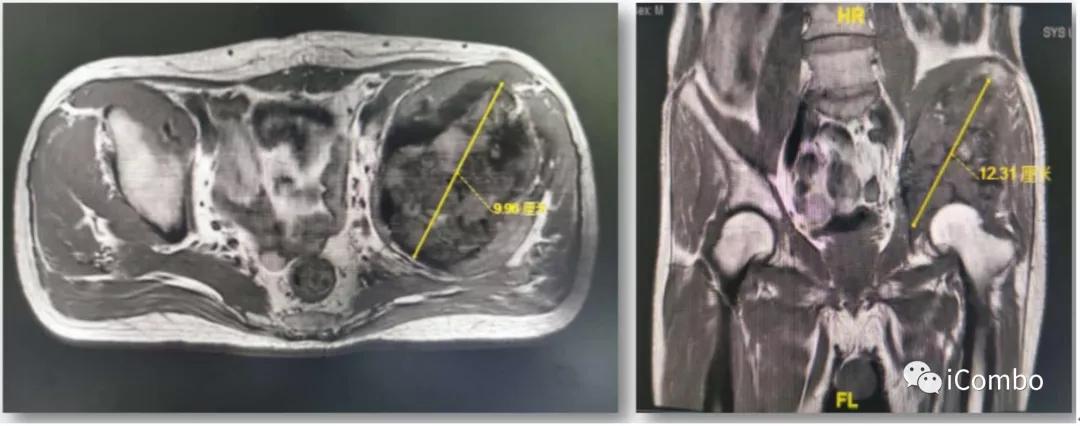

3、2019-10-21:10-8复查MRI:左侧髂骨、坐骨、耻骨骨质破坏,并软组织肿物行程,考虑转移瘤,较前缩小。肝S6/7小片状异常信号影,较前相仿。10-30,施行肝肿物的栓塞消融联合肝动脉注射PD1。治疗两次后复查,肝肿物得到了有效控制,肿物没有继续增大,原来的病灶也出现了液化坏死。

2019-10-8复查:肿物较前缩小

2020-1-8 较11-22肿物较前增大